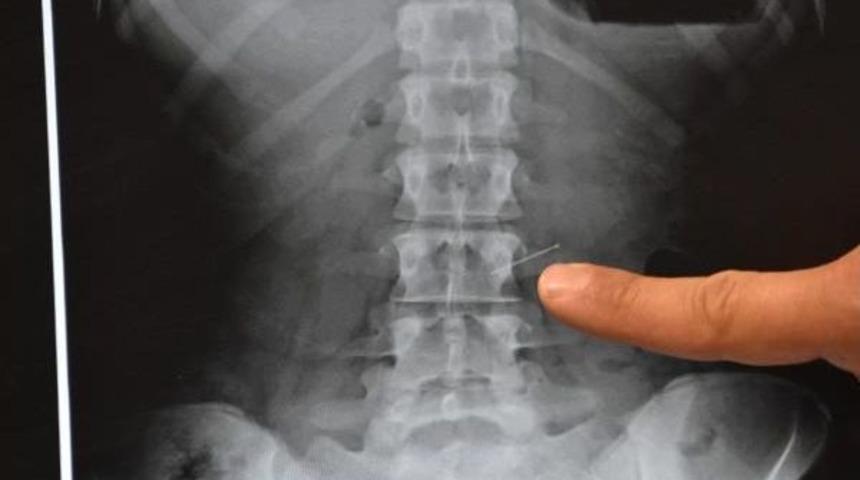

Üniversiteye giriş sınavlarına hazırlanan İlayda Adığüzel, geçen 6 Nisan Perşembe günü kursa gitmek için hazırlanırken, eşarbını tutturmak için ağzında tuttuğu 3 toplu iğneden birini öksürünce yuttu. İğneyi yuttuğunu fark eden Adıgözel durumu ailesine bildirdi. Özel Farabi Hastanesi'ne getirilen genç kız hemen ameliyata alındı. Endoskopi yöntemiyle İlayda Adıgözel'in midesinde bulunan toplu iğne çıkartıldı. İlayda Adıgözel yaşadıklarını şöyle anlattı:

Operasyonu gerçekleştiren Genel Cerrahi Uzmanı Dr. Bülent Erenoğlu, "Bize vakit kaybetmeden geldi. Biz de endoskopiyle müdahale ettik ve iğneyi başarılı bir şekilde çıkardık. İğne birkaç yerde zedeleme yapmış, onun dışında bir problem yok" dedi.